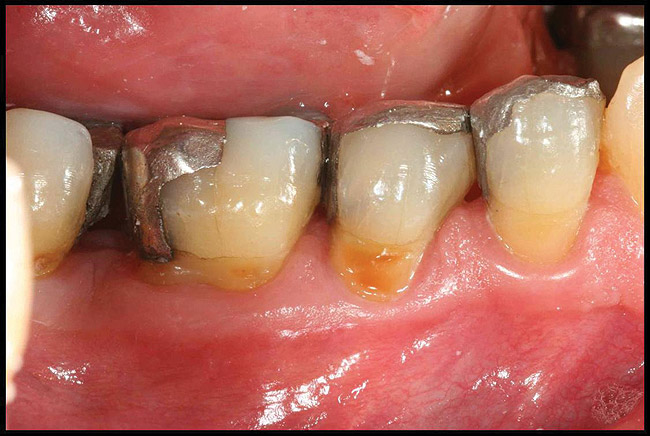

Inflammation limited to soft tissues around a dental implant may result from dental plaque colonization and is termed peri-implant mucositis. This is a reversible inflammatory condition limited to the soft tissues around the implant (without any bone loss), analogous to gingivitis around natural teeth. A diagnosis of peri-implantitis results when the inflammation spreads apically, causing progressive loss of osseointegrated supporting bone, analogous to periodontitis around natural teeth16 (Figure 2A and Figure 2B). It is essential for practitioners to be familiar with these diagnostic terms when assessing the long-term success of implants and peri-implant health (Table 1).

Figure 2a

Figureb 2  (A) Clinical and (B) radiographic views of implants at site Nos. 30 and 31 demonstrating bone loss caused by peri-implantitis after 8 years in function. Note gingival inflammation and plaque accumulation around implants.

Figure 2b